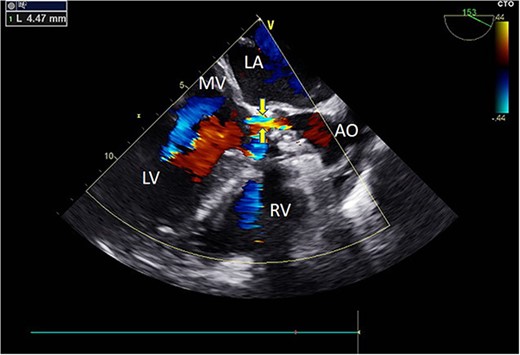

Intraoperatively, after self-expanding the aortic valve, TEE monitoring confirmed excellent cardiac function, disappearance of aortic valve regurgitation, secure anchoring of the aortic valve prosthesis, and no obstruction to the mitral valve leaflets or coronary ostia. The aortic valve velocity and pressure gradient upstream of the valve decreased compared to preoperative values, with a maximum velocity of 166 cm/s and a pressure gradient of 11 mmHg (Fig. 3). However, a periprosthetic leak with a residual width of ~4.5 mm was observed at the self-expanding valve’s interface with the native annulus (Fig. 4). Based on preoperative data, the decision was made to re-expand and reshape the prosthesis. Postdilation, TEE monitoring showed a reduction in the periprosthetic leak to 1.5 mm (Fig. 5), a significant improvement compared to predilation. Following satisfactory self-expansion results, the planned percutaneous ASD closure procedure was performed under ultrasound guidance. The closure device was securely positioned in the atrial septum, and TEE examination showed no deformation or impingement of the self-expanding valve (Fig. 6). Atrial shunting was eliminated, and the outcome exceeded expectations.

Intraoperative TEE: Long-axis aorta section shows a 1.5 mm-wide paravalvular blood flow beam, demonstrating significant improvement. Abbreviations: LA - left atrium; LV - left ventricle; RV - right ventricle; AO - aorta; MV - mitral valve.